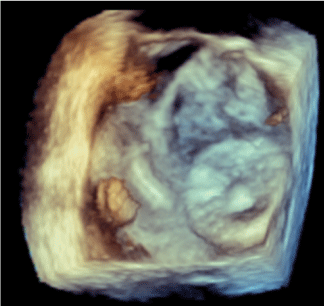

A low-contrast technique was employed for percutaneous LAA closure using a LAmbre 22/28 mm (LifeTech Scientific) device, which was successfully deployed during TEE guidance, using a low dose of contrast dye (Figures. 1-4 and Videos. 1-8). The patient’s postoperative course was uneventful, and he was successfully discharged on acetylsalicylic acid active treatment alone.

Figure 3. 3D echocardiography of LAA before device implantation

Figure 4. 3D echocardiography of LAA after device implantation